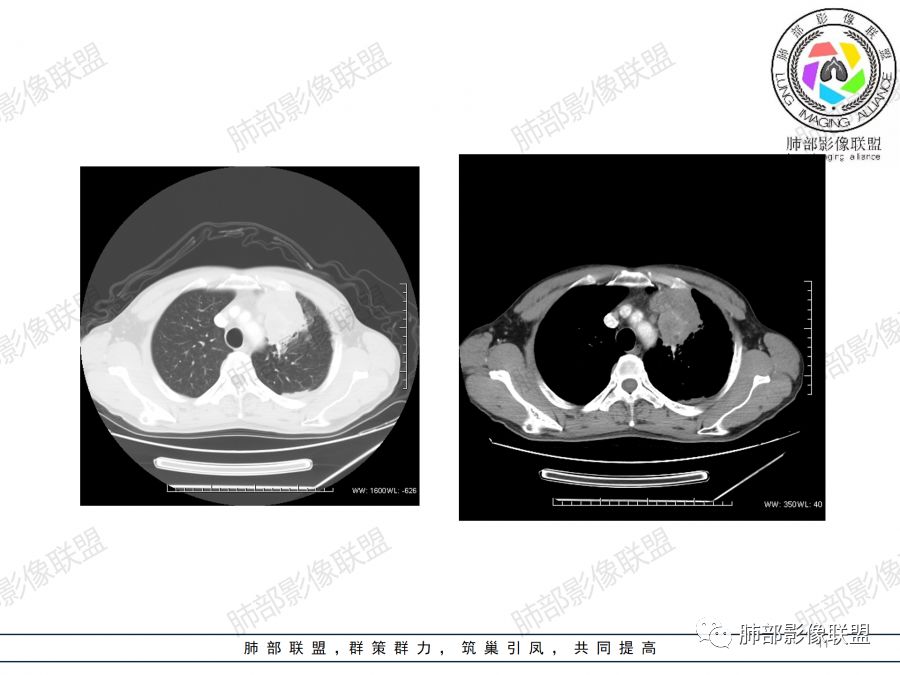

1.左肺上叶尖后段体积变化不大,病灶长轴沿支气管血管束向肺门侧生长,

2.病灶外围大,内带小,外朝内蔓延

3.病灶边缘以收缩为主,局部稍膨隆,

4.病灶整体轻中度强化,强化较均匀,局部见多个管状低密度影,边界清,考虑支气管粘液栓;病灶局部可小灶样的低密度区,未见强化,考虑坏死灶,坏死灶周围见明显强化的壁,壁清楚、光整,未见中断,倾向炎性肉芽肿的坏死;

5.病灶内血管部分走形自然,部分走形僵直、粗细不均,提示病灶有部分破坏力,但是不强;

2.双上肺多发病灶,左肺上叶病灶沿血管支气管束分布,由外朝内,以平直收缩为主,周围有斑片渗出,胸膜糊墙,支持炎性病灶或是伴有肿瘤灶可能性。

3.病灶内多支支气管粘液栓,炎性及恶性均可,但是炎性多于恶性;强化杂乱不均,病灶内小灶坏死比规则,支持炎性肉芽肿病变。